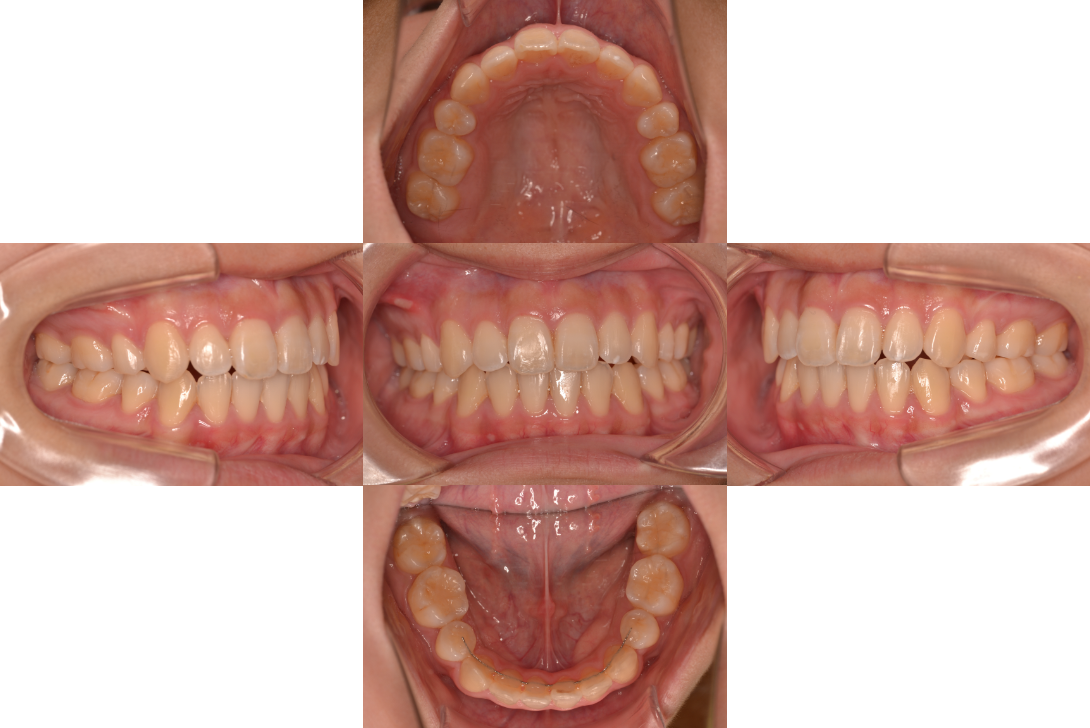

開咬(オープンバイト)を抜歯、インプラントアンカー、DBSで改善した症例

※DBSとはダイレクトボンディングシステムと呼ばれており、ブラケットにワイヤーを通して歯を動かしていく矯正治療です。

患者情報

16歳女性

主訴

前歯の隙間が気になる

行った治療内容

上顎両側4番抜歯、下顎左側1番抜歯 上顎インプラントアンカー、顎間ゴム、DBS

治療のリスク

歯根吸収、前歯部歯肉退縮

治療期間

3年6か月

※ クリックして拡大することができます。